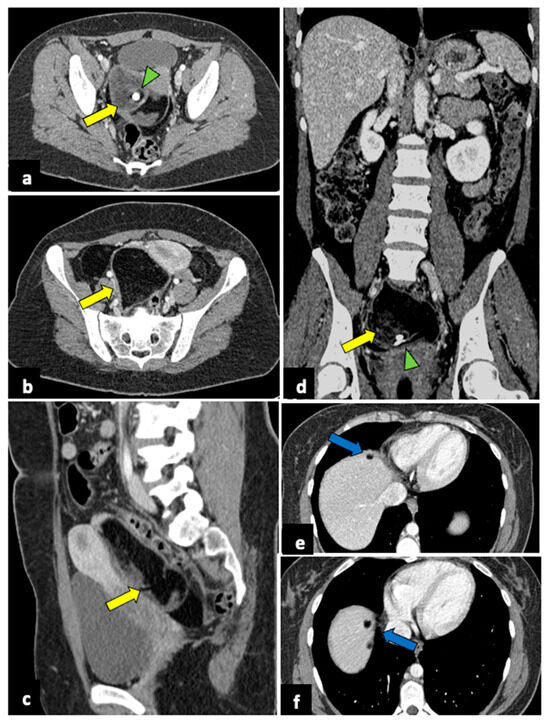

Gynaecological Causes of Acute Pelvic Pain: Common and Not-So-Common Imaging Findings

by Paolo Niccolò Franco, Alejandra García-Baizán, María Aymerich, Cesare Maino, Sofia Frade-Santos, Davide Ippolito and Milagros Otero-García

Life 2023, 13(10), 2025; https://doi.org/10.3390/life13102025 - 9 Oct 2023

In female patients, acute pelvic pain can be caused by gynaecological, gastrointestinal, and urinary tract pathologies. Due to the variety of diagnostic possibilities, the correct assessment of these patients may be challenging. The most frequent gynaecological causes of acute pelvic pain in non-pregnant [...] Read more.

In female patients, acute pelvic pain can be caused by gynaecological, gastrointestinal, and urinary tract pathologies. Due to the variety of diagnostic possibilities, the correct assessment of these patients may be challenging. The most frequent gynaecological causes of acute pelvic pain in non-pregnant women are pelvic inflammatory disease, ruptured ovarian cysts, ovarian torsion, and degeneration or torsion of uterine leiomyomas. On the other hand, spontaneous abortion, ectopic pregnancy, and placental disorders are the most frequent gynaecological entities to cause acute pelvic pain in pregnant patients. Ultrasound (US) is usually the first-line diagnostic technique because of its sensitivity across most common aetiologies and its lack of radiation exposure. Computed tomography (CT) may be performed if ultrasound findings are equivocal or if a gynaecologic disease is not initially suspected. Magnetic resonance imaging (MRI) is an extremely useful second-line technique for further characterisation after US or CT. This pictorial review aims to review the spectrum of gynaecological entities that may manifest as acute pelvic pain in the emergency department and to describe the imaging findings of these gynaecological conditions obtained with different imaging techniques. Full article

Show Figures

Figure 1